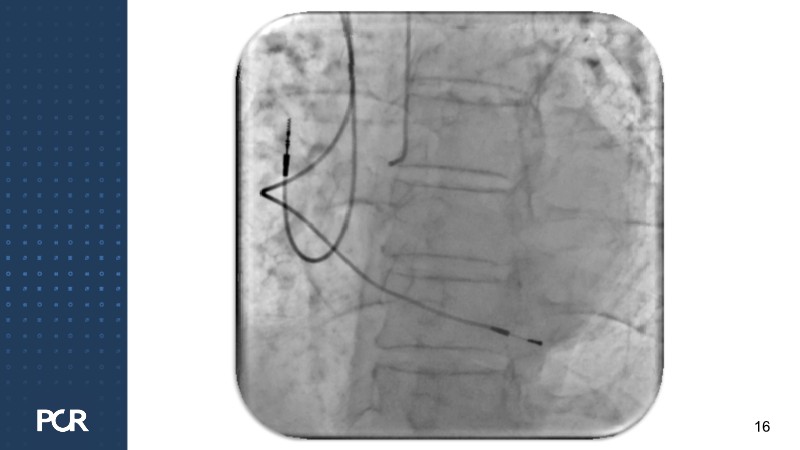

This session offers a comprehensive overview of the management of high bleeding risk (HBR) patients with multivessel disease. Through expert discussion and a live case demonstration featuring a complex elderly patient, it highlights how intracoronary imaging and physiology can guide procedural decisions and improve outcomes in this vulnerable population. The session also explores PCI strategies adapted to bleeding risk profiles, with a particular focus on the live case approach, including the use of sirolimus-eluting stents to optimise both procedural safety and long-term results.